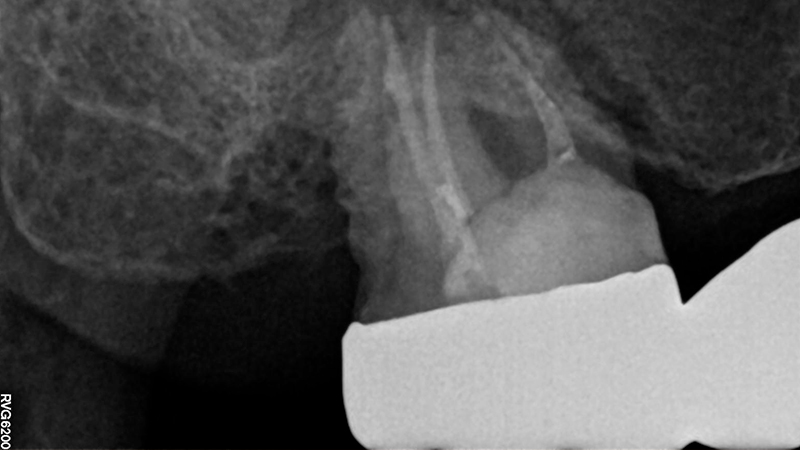

La paziente, di 68 anni, buona salute generale, presentava un grave problema al ponte 17-15-14 con dolore alla masticazione, mobilità e grave perdita ossea su 17 e 12 (Figs. 1, 2, 3).

Fig. 1 - Radiografia iniziale 17, 13, 12 con estrazione del 17 e guarigione in zona Tuber dopo 3 mesi

Fig. 2, 3 - Radiografie iniziali 17, 13, 12 con estrazione del 17 e guarigione in zona Tuber dopo 3 mesi